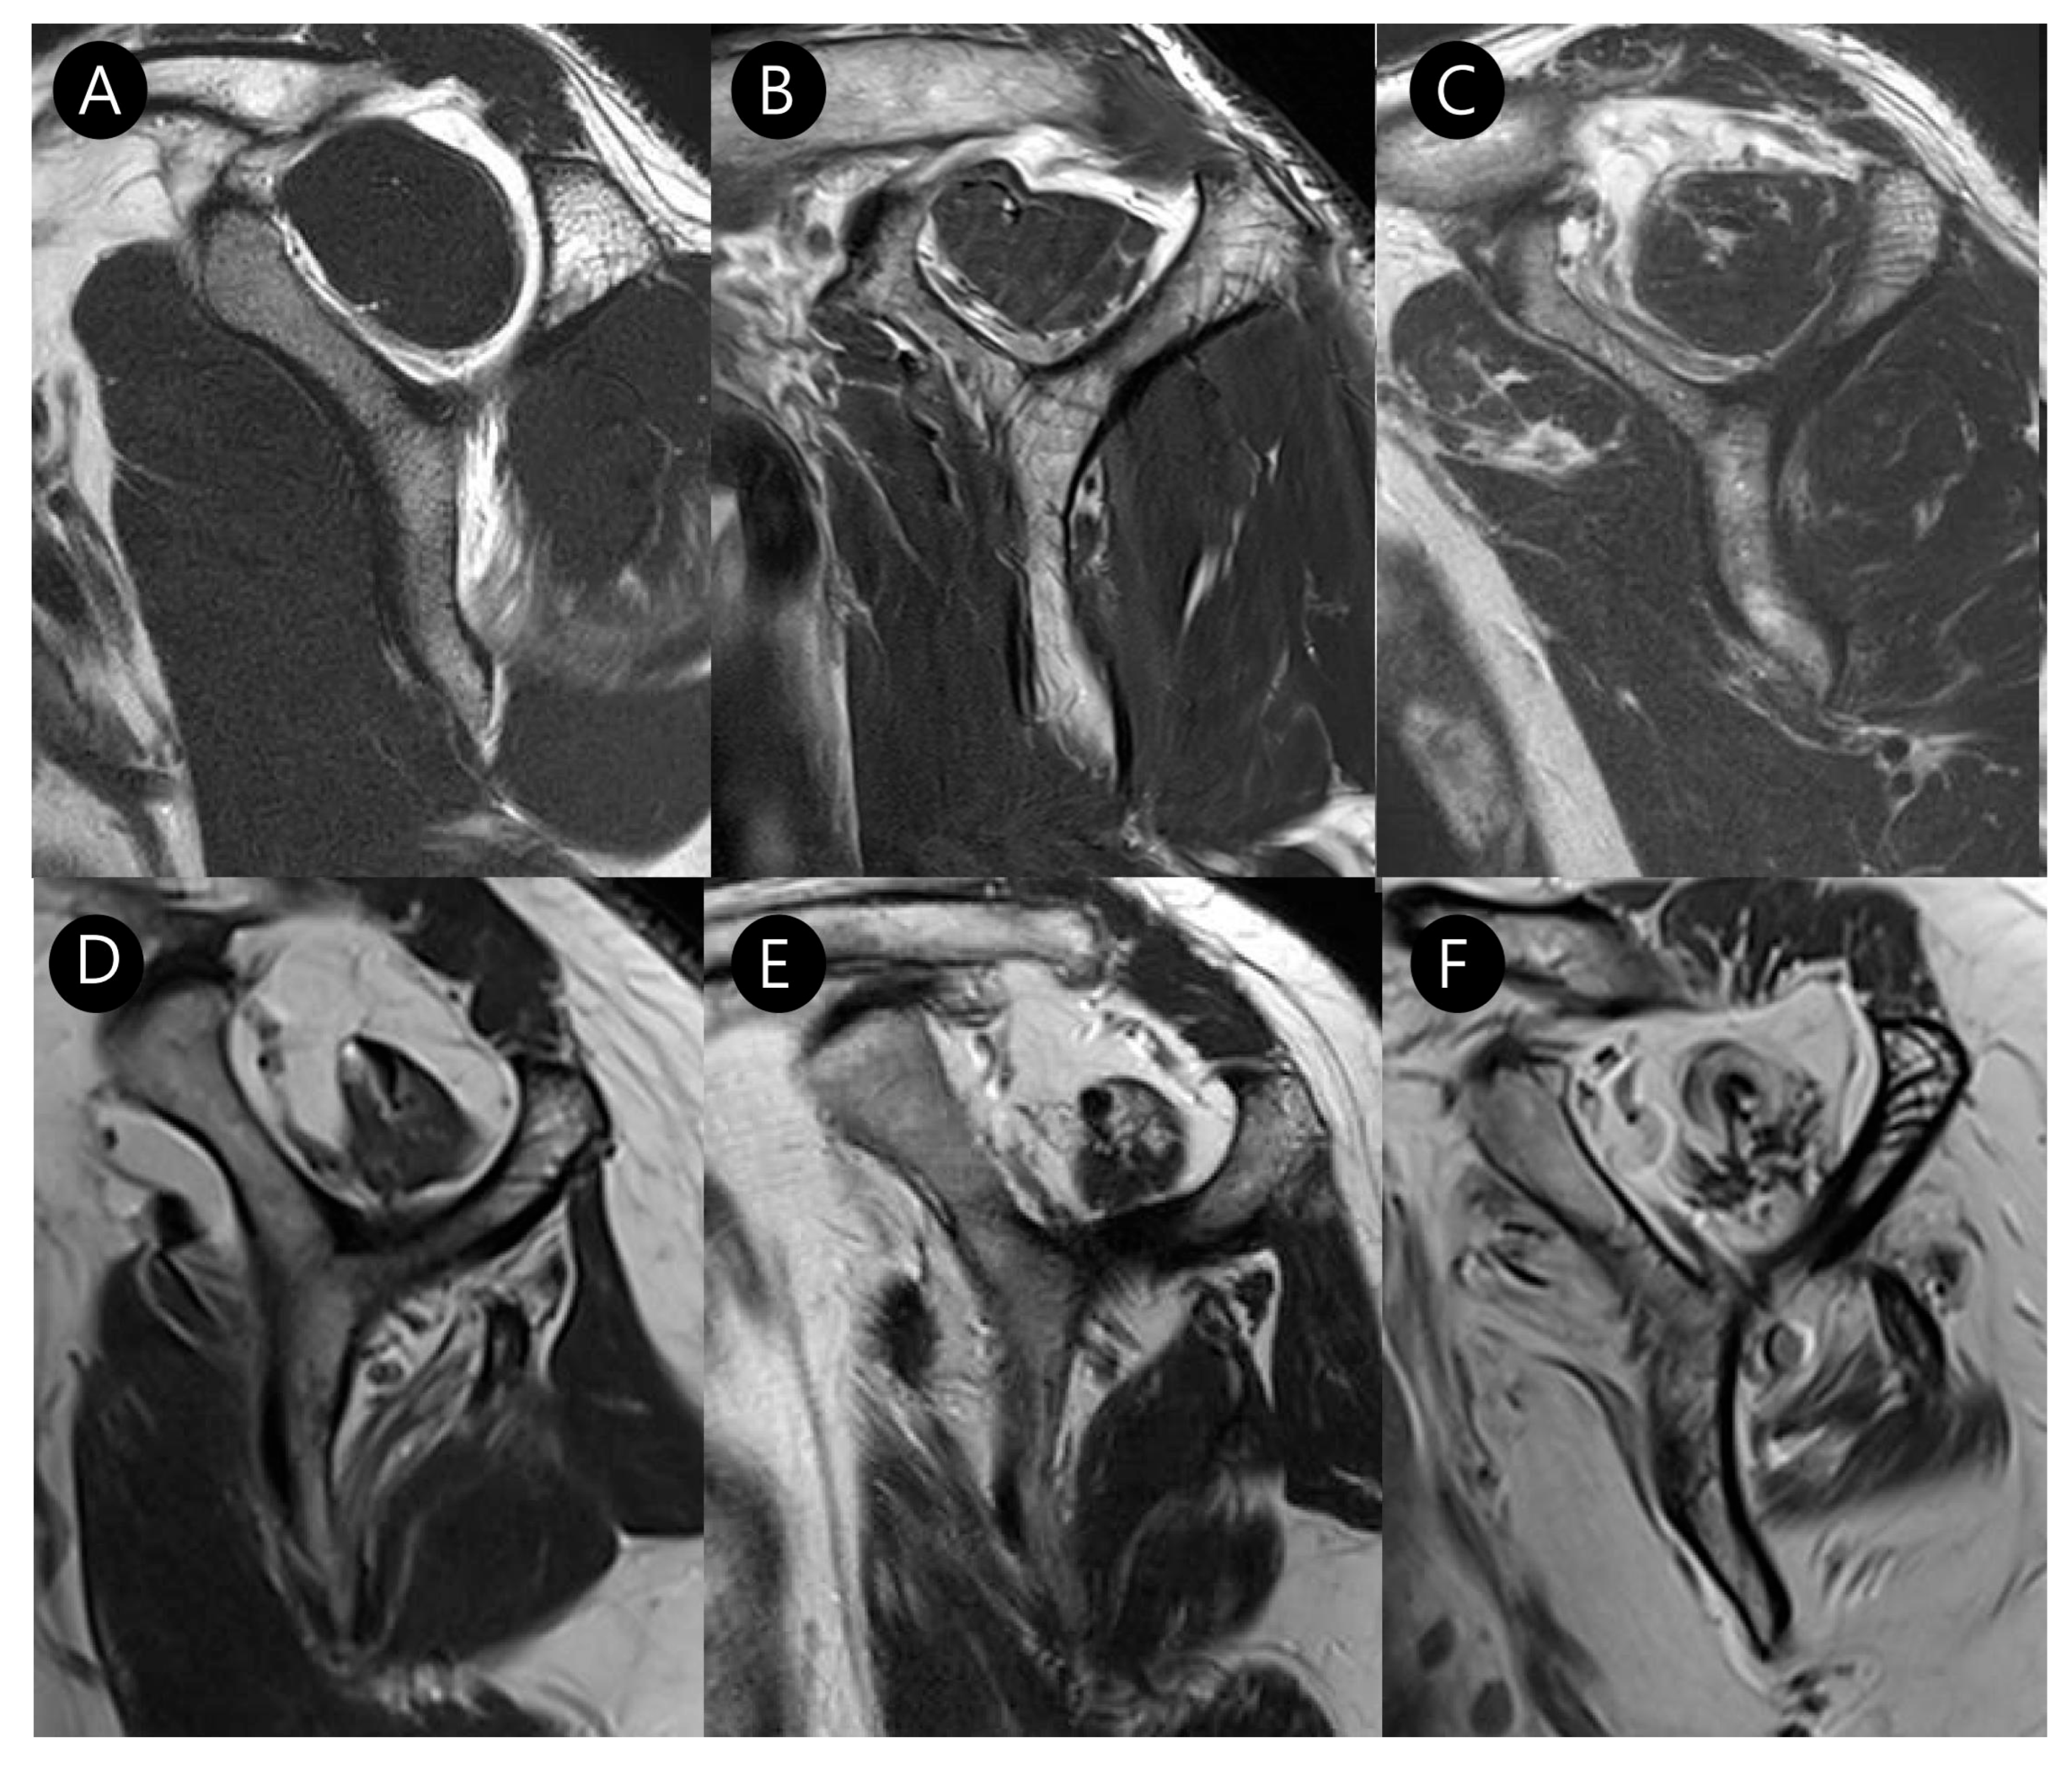

2.3. MRI Analysis

3.2. MRI Findings

| Long head biceps tendon pathologies | ||||

| Full thickness tear (%) | 4 (3.6) | 5 (15.6) | 0.040 | κ = 1.000 (p < 0.001) |

| Partial thickness tear (%) | 47 (43.9) | 25 (92.6) | <0.001 | κ = 0.981 (p < 0.001) |

| Tendinosis (%) | 76 (71.0) | 27 (100.0) | 0.003 | κ = 0.899 (p < 0.001) |

| Subluxation or dislocation (%) | 13 (12.1%) | 22 (81.5%) | <0.001 | κ = 0.853 (p < 0.001) |